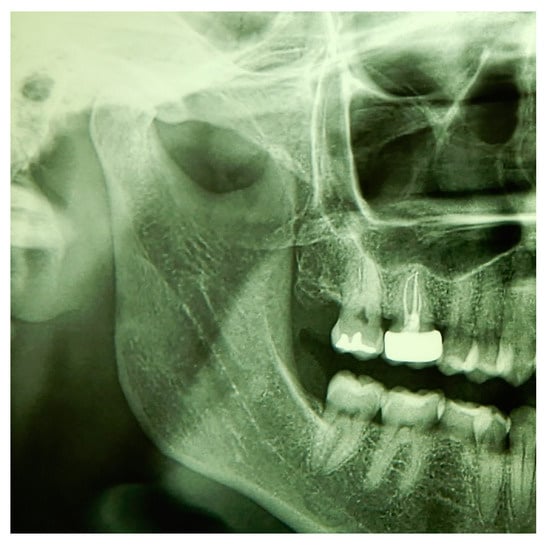

3.2. Case Report